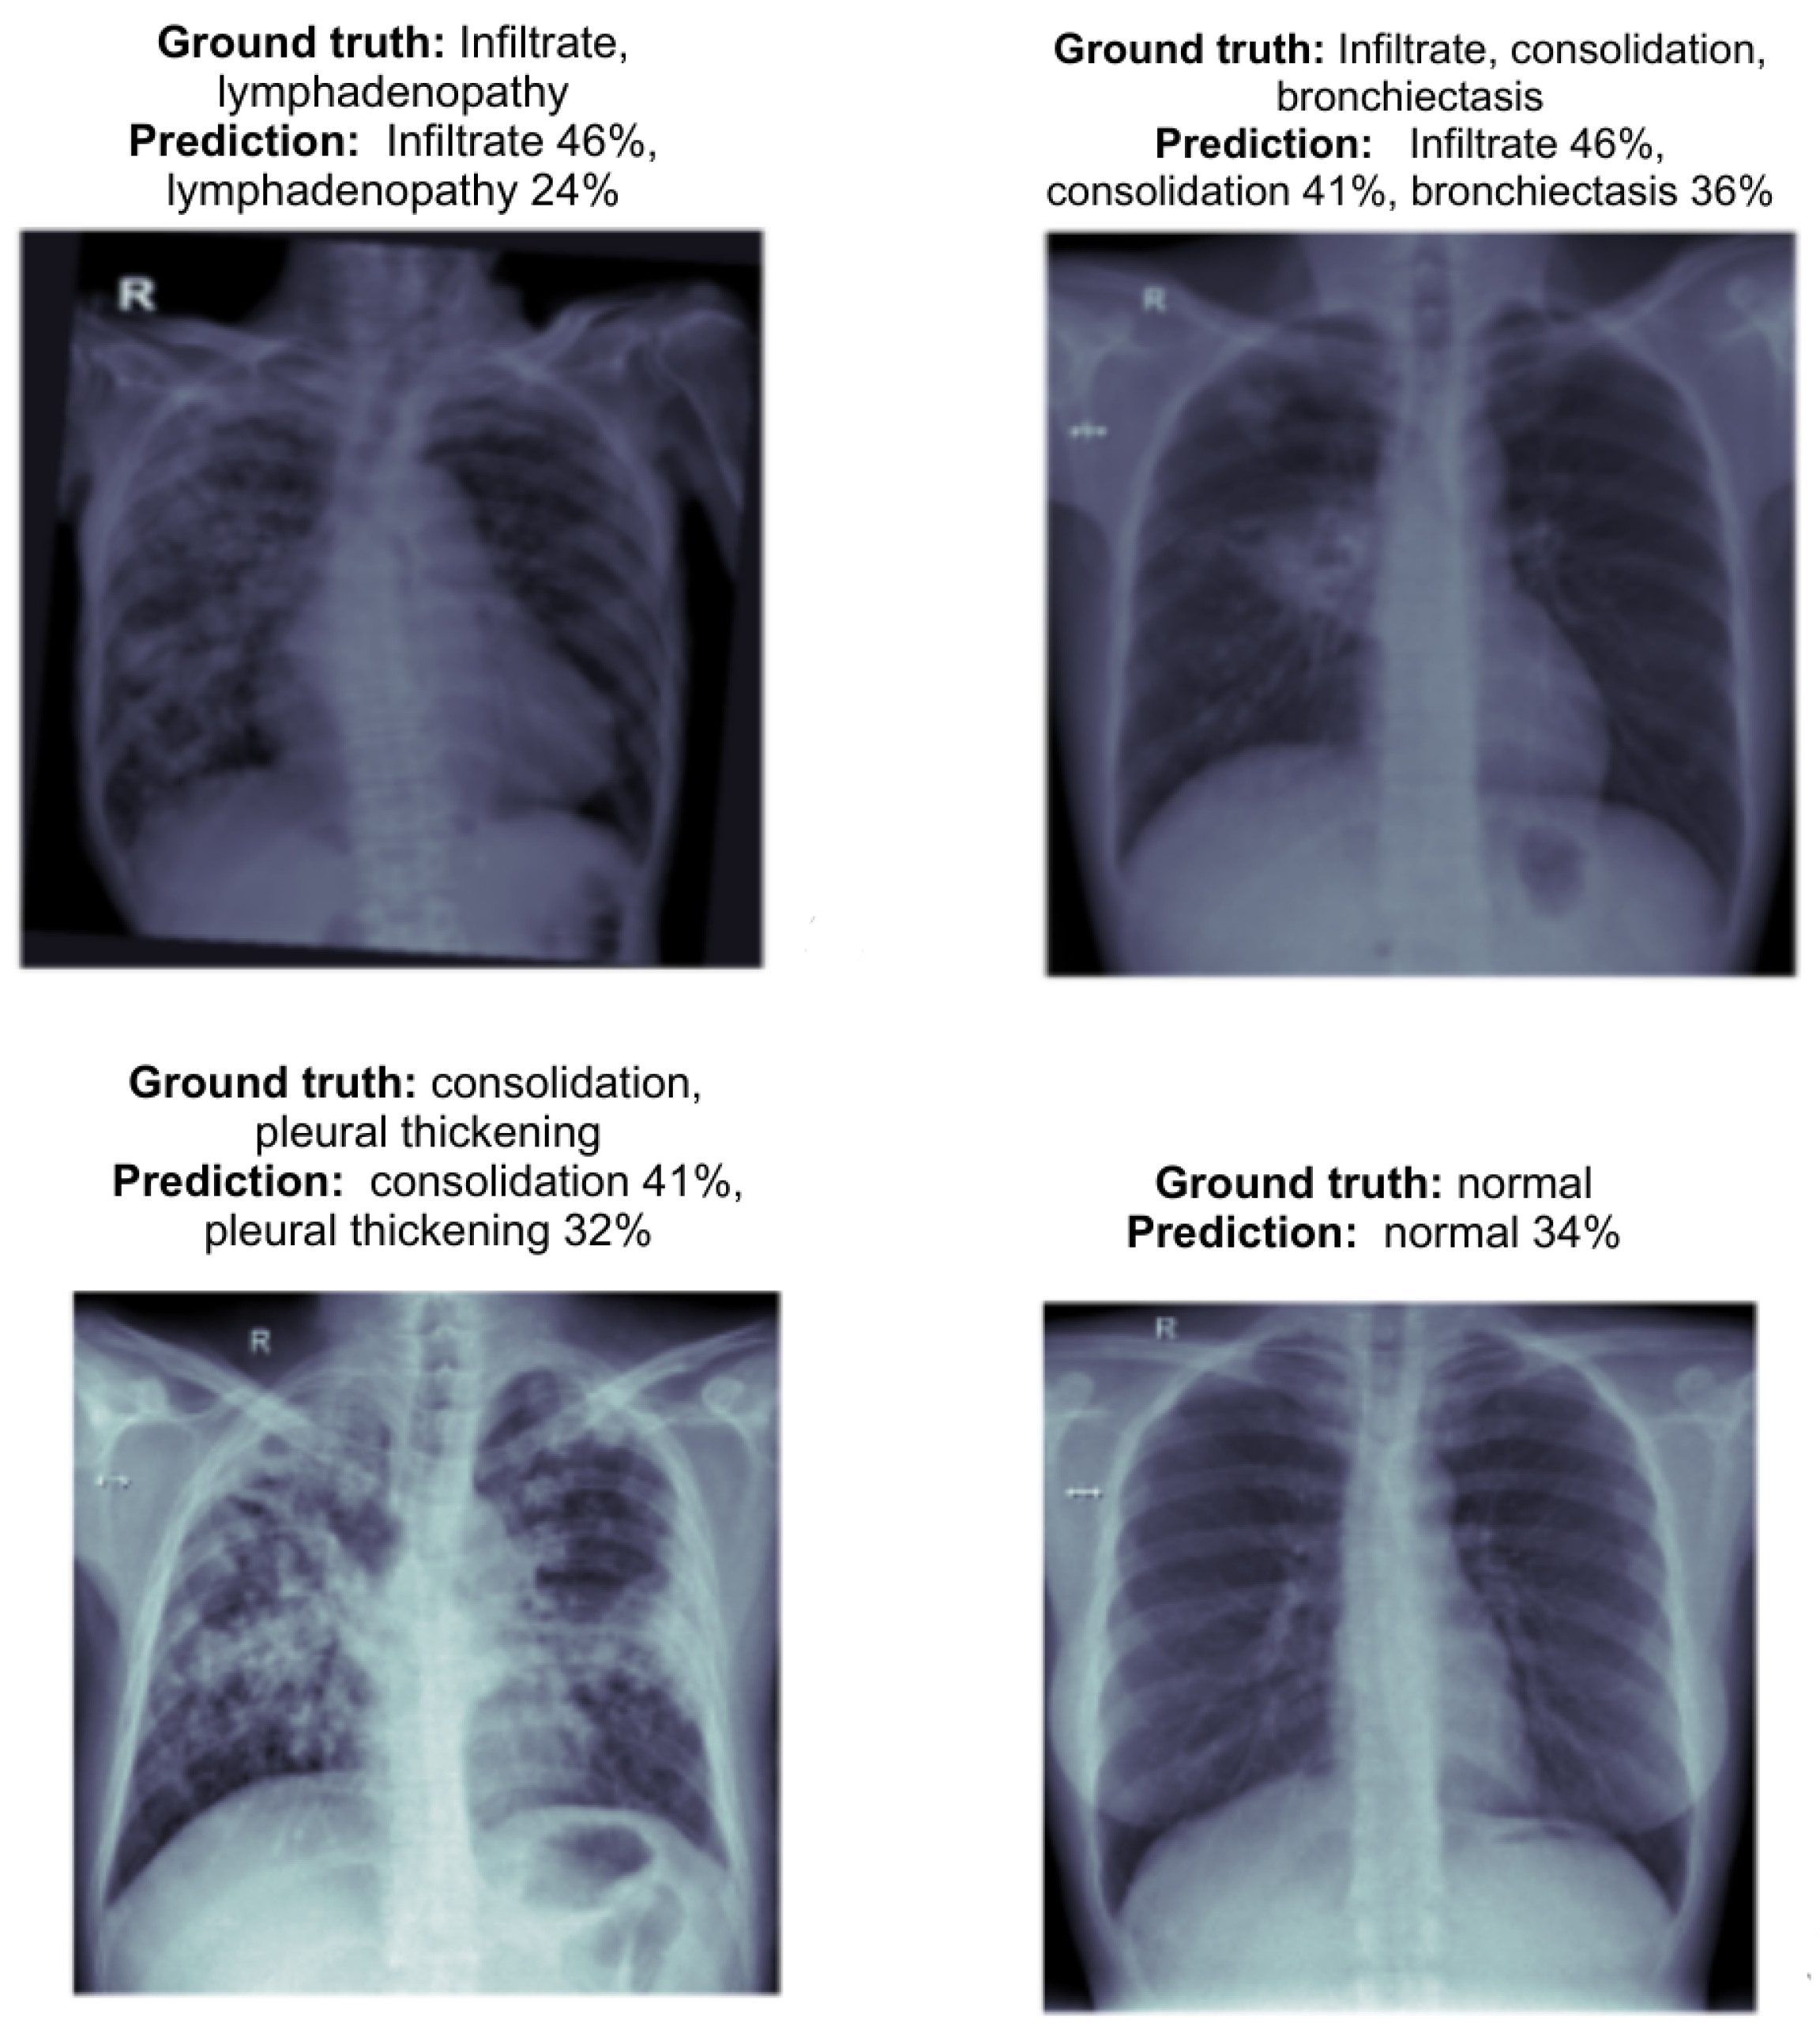

The following images as shown in the Figure 5 present the prediction outcomes from the EfficientNetV2L model. Each image includes a comparison between the actual diagnosis and the predicted diagnosis, along with the model’s confidence level for each predicted label. This analysis demonstrates the ability of both models to detect various TB-related abnormalities from chest X-ray (CXR) images.

Figure 5.

EfficientNetV2L model prediction results for normal and TB anomalies, with confidence score for each label. Each subfigure represents a chest X-ray (CXR) image with the corresponding ground truth and model predictions.

- (a)

- The ground truth is normal, and the model correctly predicts it with a confidence of 33%. The prediction aligns with the actual diagnosis, though the confidence could be higher.

- (b)

- The ground truth is consolidation and the model predicts it with 44% confidence. The model correctly identifies the abnormality, demonstrating its potential in recognizing consolidation.

- (c)

- The ground truth includes fibrosis, bronchiectasis, and pneumothorax. The model predicts these conditions with fibrosis 29%, bronchiectasis 35%, and pneumothorax 15%. These predictions reflect a reasonable overlap with the ground truth.

- (d)

- The ground truth includes consolidation and pleural thickening. The model predicts consolidation with 44% confidence and pleural thickening with 27% confidence, which aligns well with the ground truth.

First, the hybrid model showed enhanced accuracy in multi-label prediction as shown in the Figure 8. For example, in cases with multiple abnormalities such as infiltrate and lymphadenopathy, the hybrid model balanced the confidence levels between the labels, predicting infiltrate 46% and lymphadenopathy 24%. This represents a significant improvement in consistency compared to EfficientNetV2L, which struggled with lower confidence when predicting multiple labels.

Figure 8.

EfficientNetV2L model prediction results for normal and TB anomalies, with confidence score for each label.

Additionally, the hybrid model provided more balanced predictions for complex cases involving overlapping conditions like infiltrate, consolidation, and bronchiectasis. The model predicted these conditions with greater confidence: infiltrate 46%, consolidation 41%, and bronchiectasis 36%. This shows a better integration of local and global features, addressing the limitations of the individual models.

In terms of detecting pleural thickening and consolidation, the hybrid model performed significantly better than the standalone models. For instance, in one case, it predicted consolidation 41% and pleural thickening 32% with greater accuracy and balance. This improved detection of subtle abnormalities can be attributed to the hybrid model’s ability to extract both fine-grained and high-level features effectively.

Moreover, the hybrid model maintains strong performance on normal cases, predicting normal 34% with balanced confidence. This consistency across both abnormal and normal cases demonstrates the model’s robustness, reducing the likelihood of false positives, which is crucial for clinical accuracy.